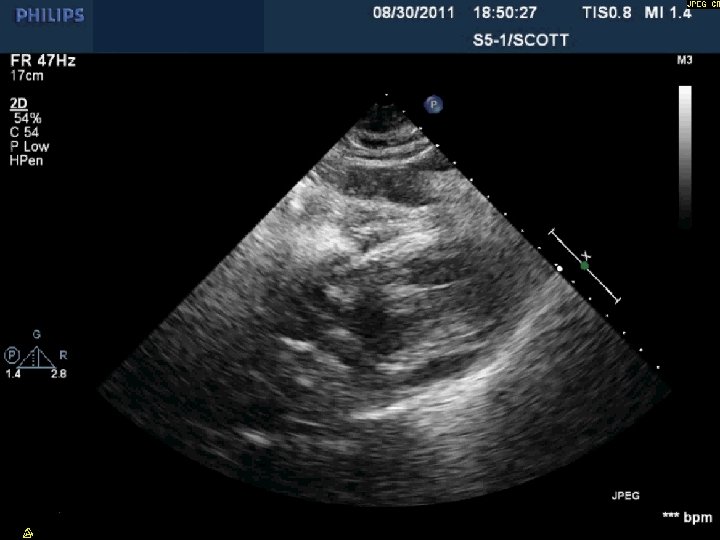

Day 2 Stable overnight No further pericardial drainage Echo shows no recurrence of effusion

Day 2 Stable overnight No further pericardial drainage Echo shows no recurrence of effusion In ICU, pericardial pigtail catheter pulled…. . Within 5 minutes, systolic blood pressure drops to <80 and bedside echo confirms recurrence of effusion Emergency pericardiocentesis draws off 650 cc immediately followed by continuous drainage of blood